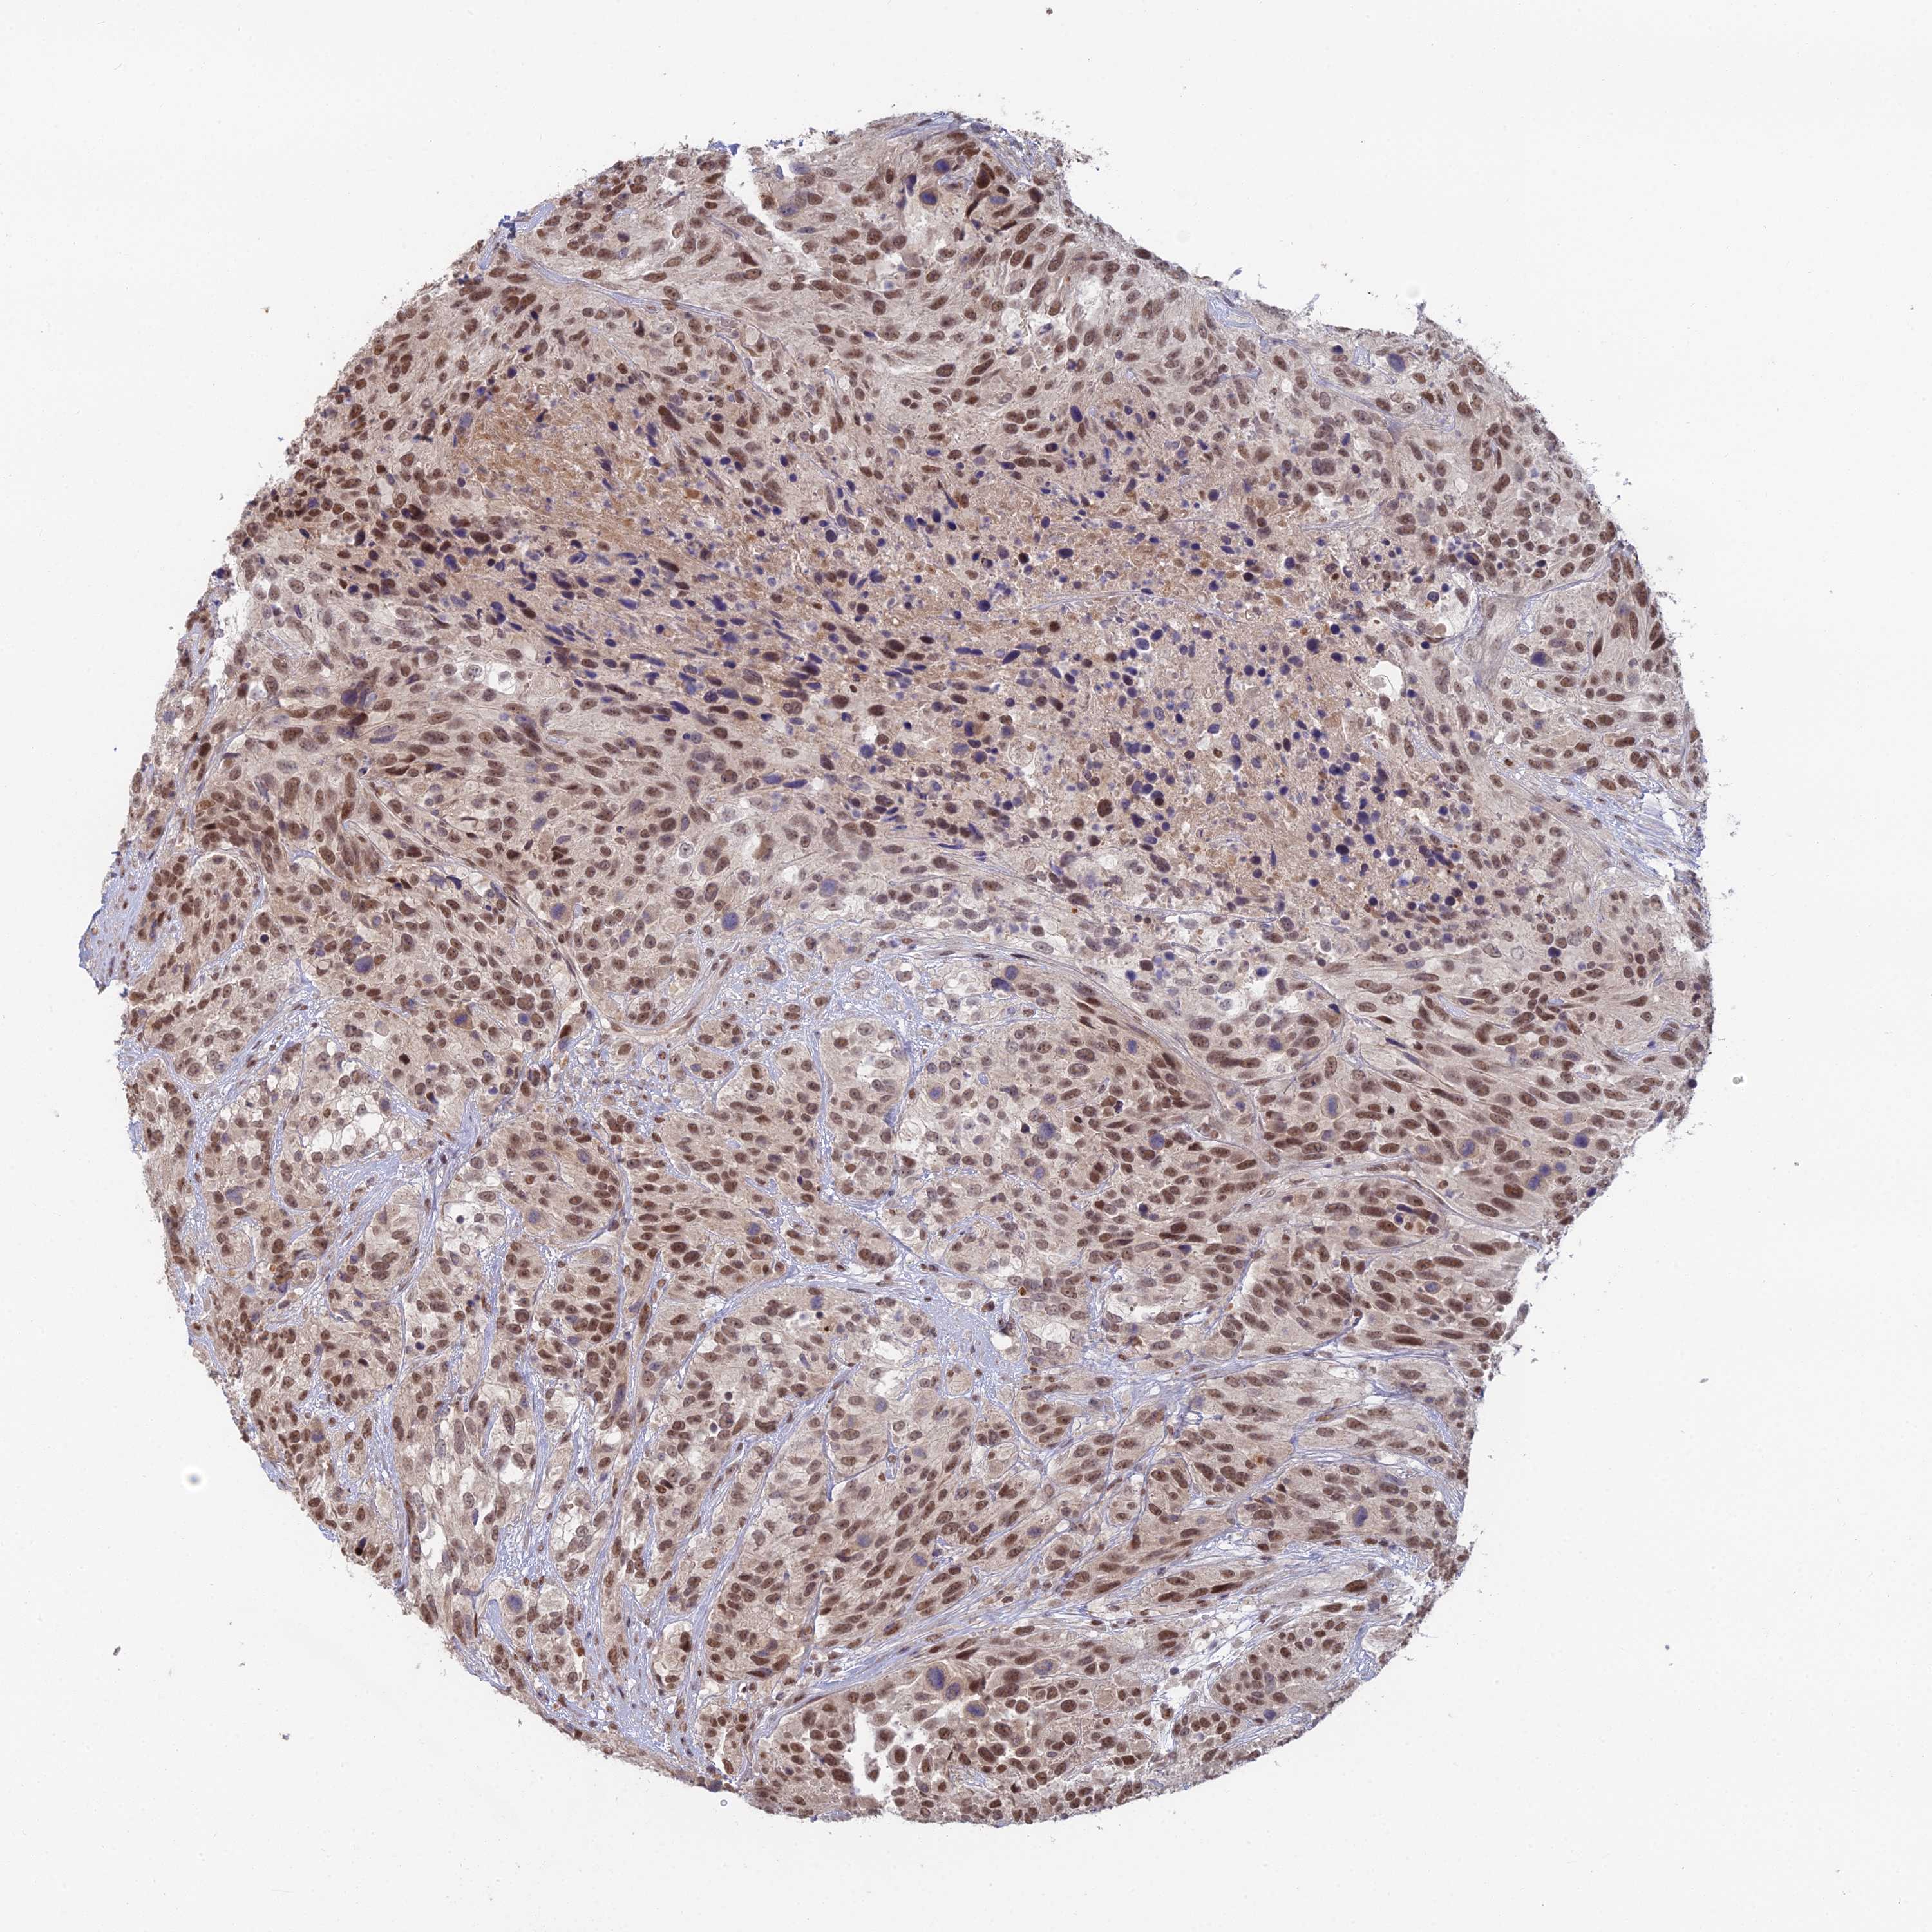

UROTHELIAL CANCER - Protein expressioni

A mouse-over function shows sample information and annotation data. Click on an image to view it in a full screen mode. Samples can be filtered based on level of antibody staining by selecting one or several of the following categories: high, medium, low and not detected. The assay and annotation is described here.

Note that samples used for immunohistochemistry by the Human Protein Atlas do not correspond to samples in the TCGA dataset.

Antibody stainingi

Antibody staining in the annotated cell types in the current human tissue is reported as not detected, low, medium, or high, based on conventional immunohistochemistry profiling in selected tissues. This score is based on the combination of the staining intensity and fraction of stained cells.

Each image is clickable and will lead to virtual microscopy that enables deeper exploration of all samples and also displays staining intensity scores, fraction scores and subcellular localization as well as patient and tissue information for each sample.

Antibody HPA043375

Antibody HPA043389

Staining

High

Medium

Low

Not detected

Intensity

Strong

Moderate

Weak

Negative

Quantity

>75%

75%-25%

<25%

None

Location

Nuclear

Cytoplasmic/membranous

Cytoplasmic/membranous,nuclear

Urothelial carcinoma, High grade

Urothelial carcinoma, Low grade